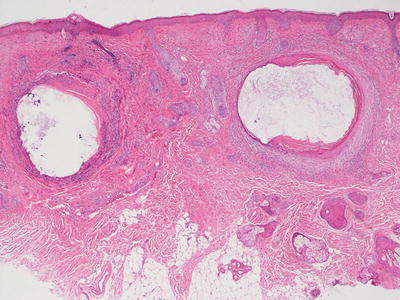

The changes of acne vulgaris include sebaceous hyperplasia and varying degrees of inflammation within and around the pilosebaceous units. Mild cases may demonstrate only a scant lymphohistiocytic infiltrate at the level of the follicular infundibulum with focal follicular spongiosis. More florid cases will show comedones with cystic dilatation of the follicular ostia with keratin plugging (Figs. 10.7 and 10.8). Neutrophilic abscesses can be found within follicular outflow tracts or in the adjacent dermis. Follicular plugging can result in the development of follicular cysts, and in some cases accompanied by marked inflammation. In more extensive cases, there may be disruption of the follicular epithelia, extrusion of keratin into the dermis, and marked inflammation. A granulomatous response with multinucleated giant cells and abundant histiocytes is not unusual in these cases.

Fig. 10.7

Dilated keratin-filled follicles are surrounded by an inflammatory infiltrate in acne vulgaris

Fig. 10.8

Keratin fills a cystically dilated hair follicle in a comedone in acne vulgaris